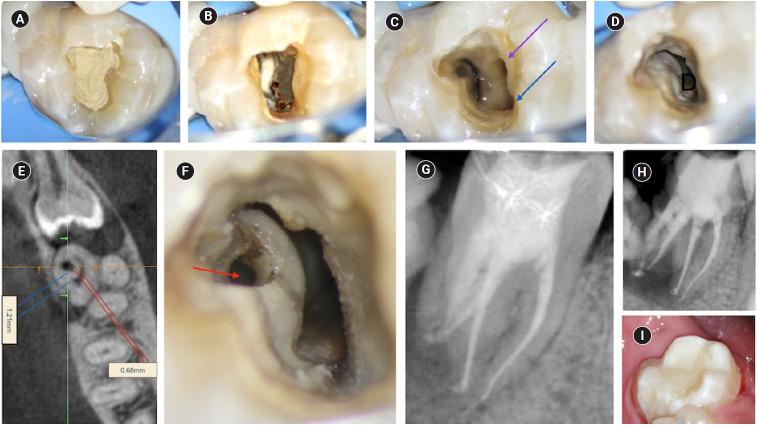

The present case report describes the endodontic treatment of a type III B dens invaginatus (DI) in a three-rooted mandibular second molar since the invagination invades the root and extends apically. Clinical and cone-beam computed tomography examination of the mandibular second molar showed a broadened coronal morphology, DI, a third root, periapical radiolucency, and compression of a distal root canal by the invagination, which developed an atypical semilunar shape. The tooth was diagnosed with pulpal necrosis, symptomatic apical, and peri-invagination periodontitis. Consequently, three-dimensional virtual reconstruction was conducted to improve anatomical interpretation and case planning and accelerate the intraoperative phase by reducing operator stress and minimizing intraoperative variables. The present case report aims to raise awareness of the existence of DI on the mandibular second molar.

摘要

本病例报告描述了一例下颌第二磨牙III型B型牙内陷(DI)的根管治疗,因为该牙内陷侵入牙根并向根尖延伸。对该下颌第二磨牙进行的临床和锥形束计算机断层扫描检查显示,其冠部形态变宽、存在牙内陷、有第三根、根尖周透射区以及牙内陷对远中根管造成压迫,形成了非典型的半月形。该牙齿被诊断为牙髓坏死、有症状的根尖周炎和牙内陷周围牙周炎。因此,进行了三维虚拟重建,以改善解剖结构解读和病例规划,并通过减轻术者压力和减少术中变量来加速手术进程。本病例报告旨在提高对下颌第二磨牙存在牙内陷情况的认识。